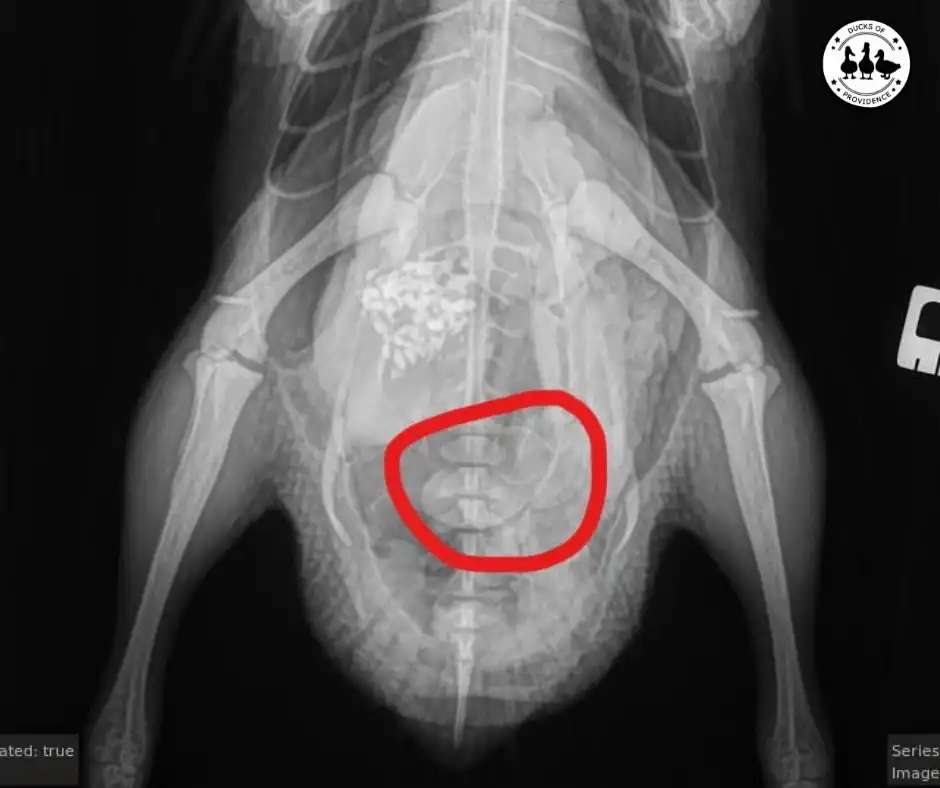

Egg binding, or dystocia, is a common problem in domestic ducks. It occurs when a duck cannot pass an egg that has been formed, either due to a physical obstruction or a lack of muscle tone in the reproductive tract. This can be a serious issue for ducks, leading to infection, injury, and even death if left untreated.

Several signs indicate that a duck may be egg-bound. These include a swollen abdomen, lethargy, a lack of appetite, and straining to lay an egg without success. Sometimes, a duck may also show signs of pain or discomfort. Below is a comprehensive list of possible symptoms:

If you suspect a duck is egg-bound, seeking veterinary care as soon as possible is important. The egg could block feces from getting released. Your duck can die within 24 hours if this happens. So check to see if your duck still poops.

In some cases, physical obstructions within the reproductive tract can impede the passage of eggs, leading to egg binding. Tumors, cysts, or other abnormalities may obstruct the oviduct, preventing the egg from progressing along its natural path. These obstructions can pose significant challenges and may require veterinary intervention to resolve.

Surgical Intervention

However, surgical intervention may be necessary if the egg binding in your duck is caused by a physical obstruction within the reproductive tract. A skilled avian veterinarian can perform a surgical procedure to remove the obstruction, whether a tumor, cyst, or other anatomical anomaly, allowing the egg to be safely expelled. Surgery may also be required to repair any damage to the reproductive organs caused by the obstruction or prolonged egg retention.